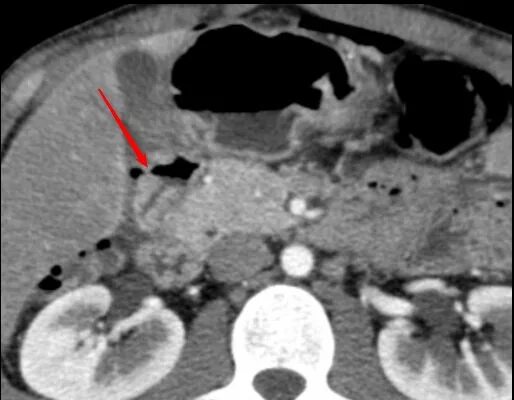

Язва желудка кт